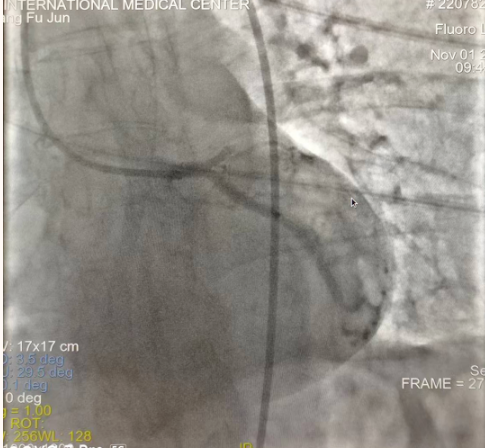

閉塞的血管再通時(shí)間取決于急救時(shí)長、轉(zhuǎn)運(yùn)時(shí)長和治療時(shí)長,在前兩方面,醫(yī)院已為患者爭(zhēng)取了最短時(shí)間。患者家屬遠(yuǎn)在陜北,雖然已在趕來的路上,但最快抵達(dá)西安也要3小時(shí),在與患者家屬電話溝通同意急診手術(shù)后,醫(yī)療總值班代家屬簽字,康曉軍在請(qǐng)示心臟病醫(yī)院王海昌院長及心臟內(nèi)科CCU尚福軍主任后,積極進(jìn)行術(shù)前準(zhǔn)備。在沒有家屬陪同、沒有交費(fèi)、沒有辦入院手續(xù)的情況下,患者經(jīng)胸痛中心綠色通道被送往心臟冠脈介入手術(shù)室,打通了完全閉塞的心臟前降支近段血管。